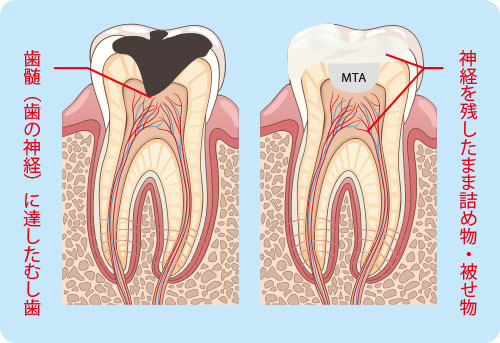

そこで歯の神経がまだ残せると判断した場合や、歯が残せると判断した場合に素晴らしい役目を果たしてくれるのが【MTAセメント】です。

歯や歯の神経を残すためには、なくてはならないセメントであると言えます。

MTAセメントは虫歯治療において、以下のような効果を発揮します。

虫歯が象牙質にまで達し、神経に近くなる、または露髄といって歯の神経が露出してしまった場合に、適切な処置を行った後、MTAセメントによって封鎖する(歯髄保存療法といいます)を行うことによって、歯の神経を残すことができます。